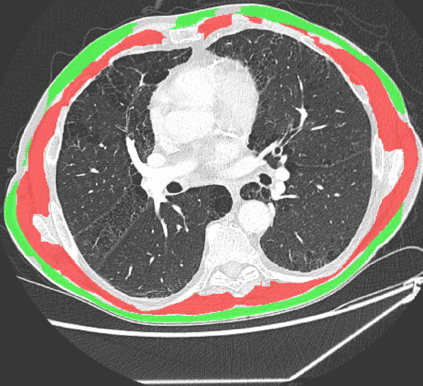

The COVID-19 pandemic has had a considerable impact on day-to-day life. Tackling the disease by providing the necessary resources to the affected is of paramount importance. However, estimation of the required resources is not a trivial task given the number of factors which determine the requirement. This issue can be addressed by predicting the probability that an infected patient requires Intensive Care Unit (ICU) support and the importance of each of the factors that influence it. Moreover, to assist the doctors in determining the patients at high risk of fatality, the probability of death is also calculated. For determining both the patient outcomes (ICU admission and death), a novel methodology is proposed by combining multi-modal features, extracted from Computed Tomography (CT) scans and Electronic Health Record (EHR) data. Deep learning models are leveraged to extract quantitative features from CT scans. These features combined with those directly read from the EHR database are fed into machine learning models to eventually output the probabilities of patient outcomes. This work demonstrates both the ability to apply a broad set of deep learning methods for general quantification of Chest CT scans and the ability to link these quantitative metrics to patient outcomes. The effectiveness of the proposed method is shown by testing it on an internally curated dataset, achieving a mean area under Receiver operating characteristic curve (AUC) of 0.77 on ICU admission prediction and a mean AUC of 0.73 on death prediction using the best performing classifiers.